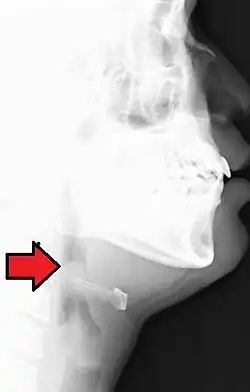

Nemoc se diagnostikuje pomocí laryngoskopického vyšetření, v průběhu něhož může při akutní epiglotitidě dojít ke stahu dýchacích cest. Proto se využívá také CT, díky němuž lze podle velikosti příklopky zjistit, zda se jedná o akutní epiglottidu. U některých pacientů se objeví komplikace v podobě zápalu plic, lymfadenopatie nebo septické artritidy.